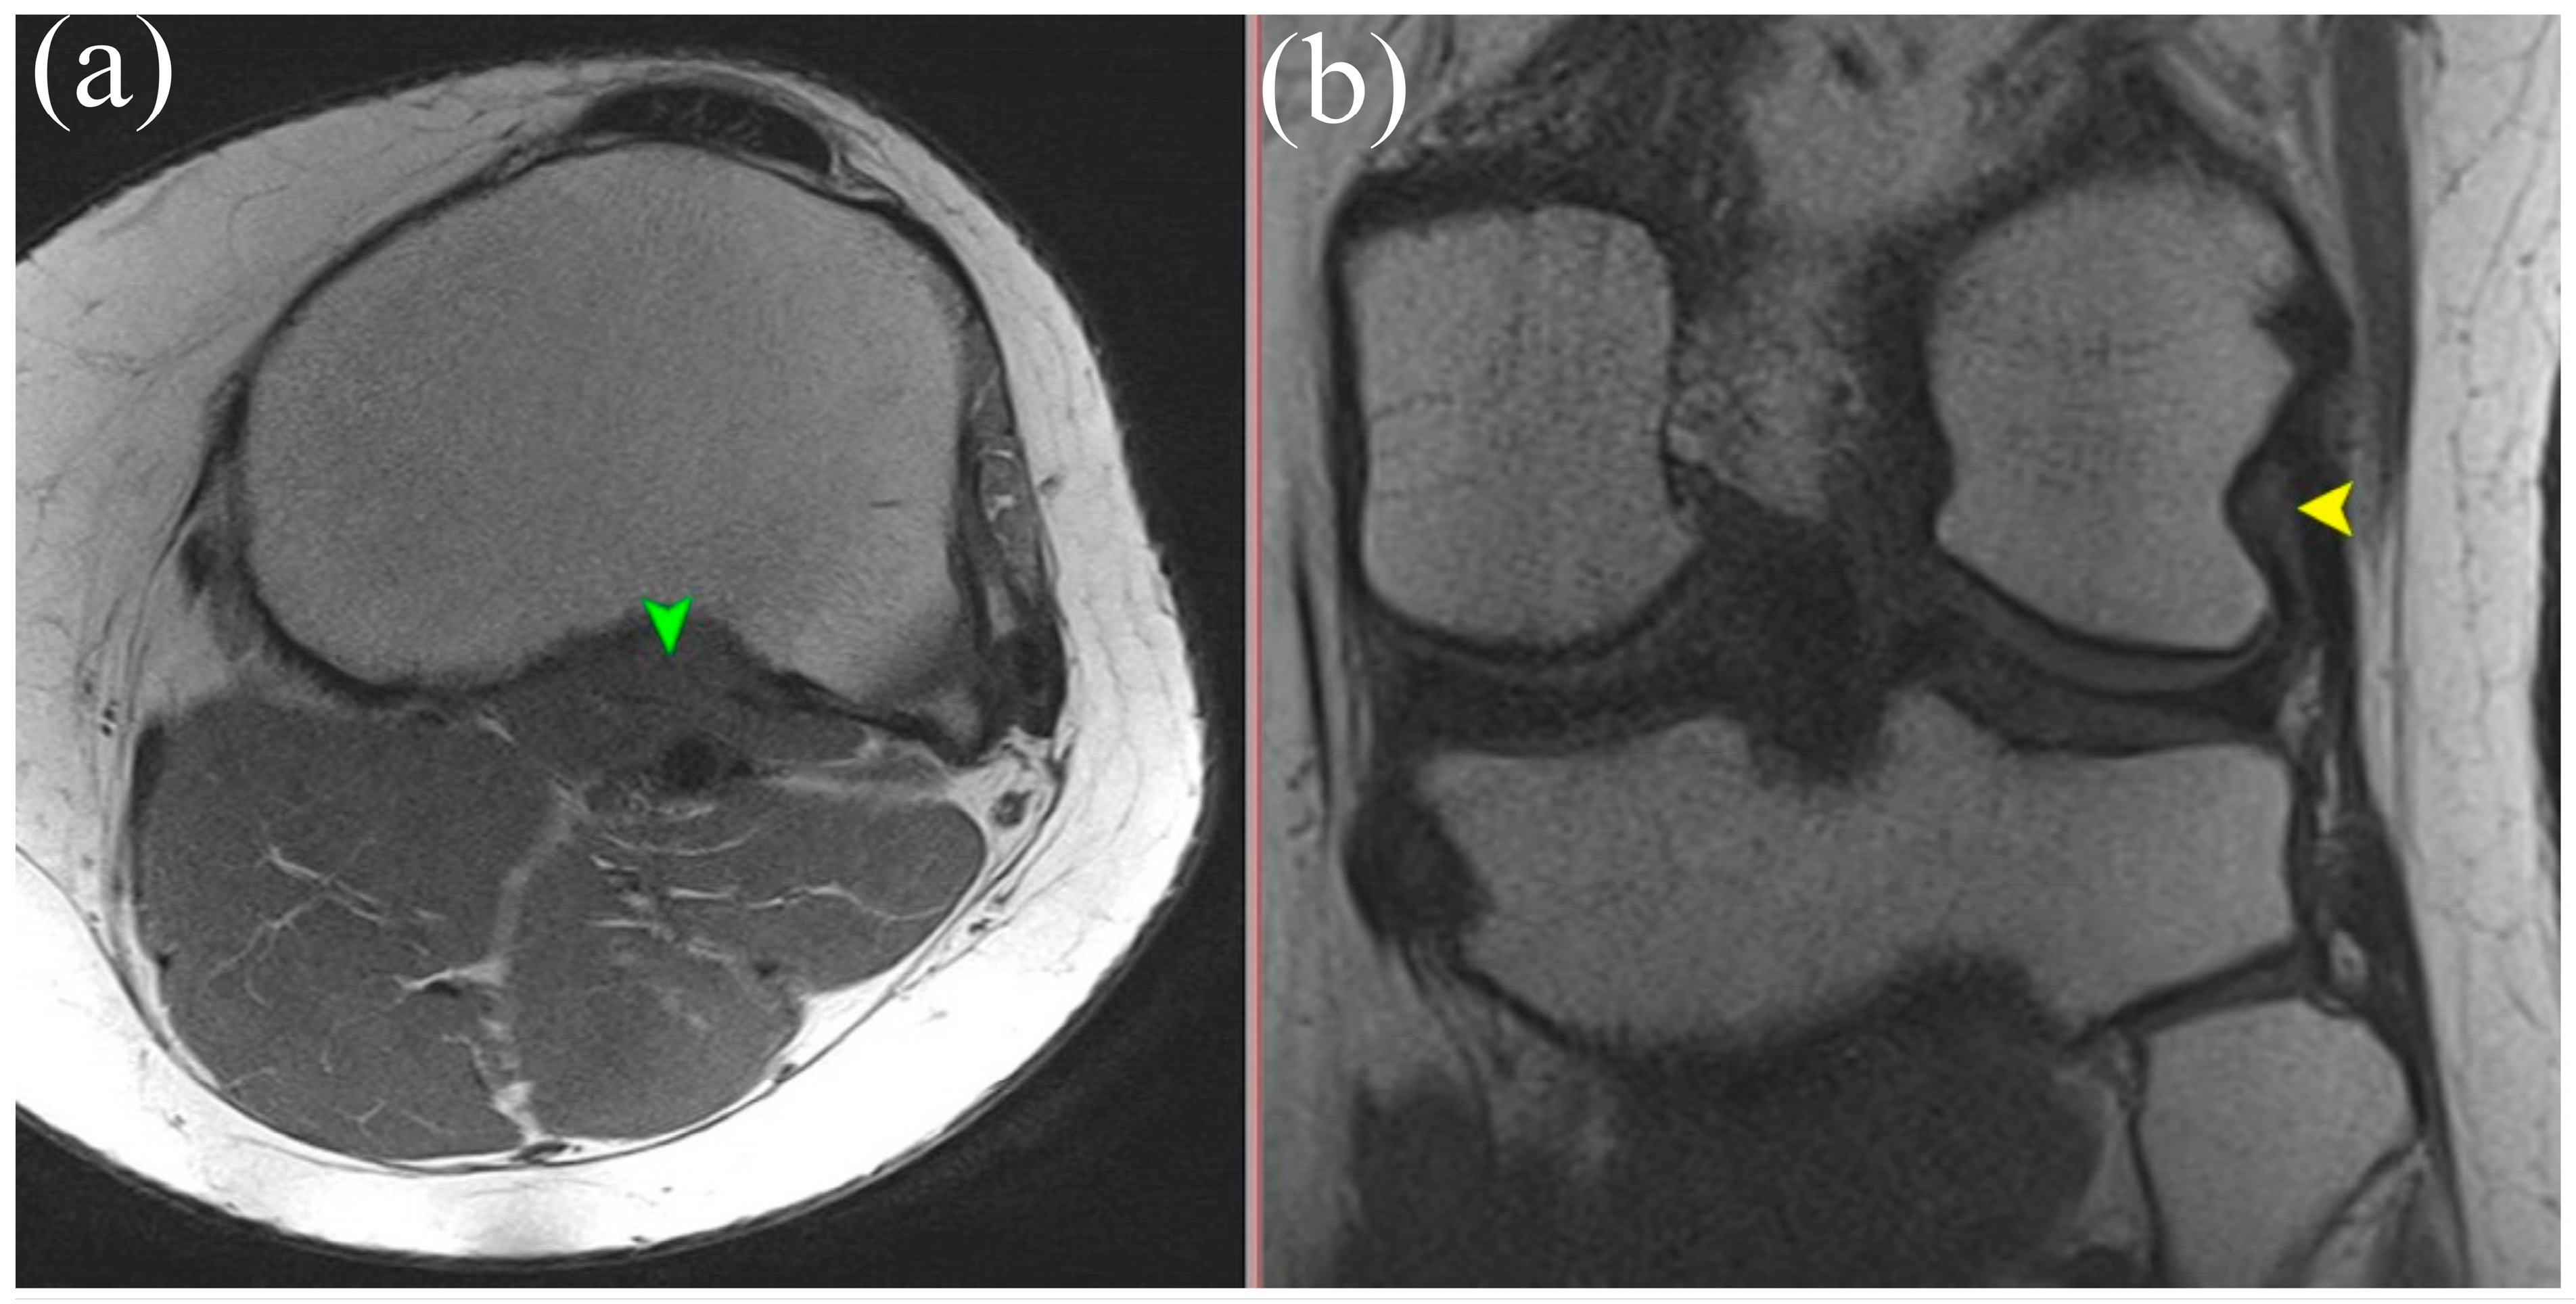

MRI is the gold standard for evaluating soft tissue structures in the knee, including the PT. Optimal visualization of the tendon is achieved using T1 and T2 weighted sequences (Figure 1 and Figure 2) with fat saturation in axial, coronal, and sagittal planes. The PT appears as a low signal intensity structure running obliquely from the lateral femoral condyle to the posteromedial tibia [1,15].

Figure 1.

T2 sequence showing the tendon and multiplanar reconstruction. Yellow arrows indicate the tendon of the PM. Green arrows indicate the muscle belly of the PT.

(a) Axial T1-weighted MRI showing the muscle belly of the popliteus muscle (green arrowhead). (b) Coronal T2-weighted MRI illustrating the tendinous portion of the popliteus (yellow arrowhead). Both panels demonstrate anatomical relationships of the popliteus tendon complex relevant for imaging-based identification.